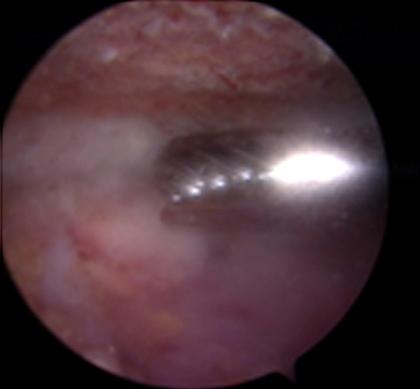

ตัวอย่างการผ่าตัดผ่านกล้องรักษากระดูกงอกทับเส้นเอ็นหัวไหล่

การรักษาโดยการผ่าตัดผ่านกล้องไหล่ ถือเป็นมาตรฐานการรักษาโรคของข้อไหล่ที่ยอมรับกันทั่วโลก นอกจากสามารถให้การวินิจฉัยแล้วยังเป็นการรักษาในคราวเดียวกัน กรณีที่เหมาะสมต่อการผ่าตัดส่องกล้องข้อไหล่ คือโรคของข้อไหล่ที่รักษาด้วยวิธีอนุรักษ์นิยมอย่างเต็มที่แล้ว ซึ่งประกอบด้วย การรับประทานยาแก้ปวด เช่น พาราเซตามอล, ยาลดอาการอักเสบที่ไม่ใช่สเตียรอยด์ และยาคลายกล้ามเนื้อ ร่วมกับกายภาพบำบัดอย่างเต็มที่แล้วไม่ได้ผล เป็นเวลาอย่างน้อย 3-6 เดือน จึงพิจารณานำวีธีการผ่าตัดผ่านกล้องมารักษา ซึ่งจะทำการเปิดแผลขนาด 0.5 - 1 ซ.ม. ประมาณ 2-3 แผล เพื่อใส่กล้องขนาดประมาณ 4 มิลลิเมตร ใส่น้ำเกลือเข้าไปในข้อเพื่อขยายพื้นที่ในการผ่าตัด และใส่อุปกรณ์การผ่าตัดเพื่อทำการรักษา พบว่าผลการรักษาไม่แตกต่างจากการรักษาโดยการเปิดแผล แต่กลับฟื้นตัวได้เร็วขึ้น